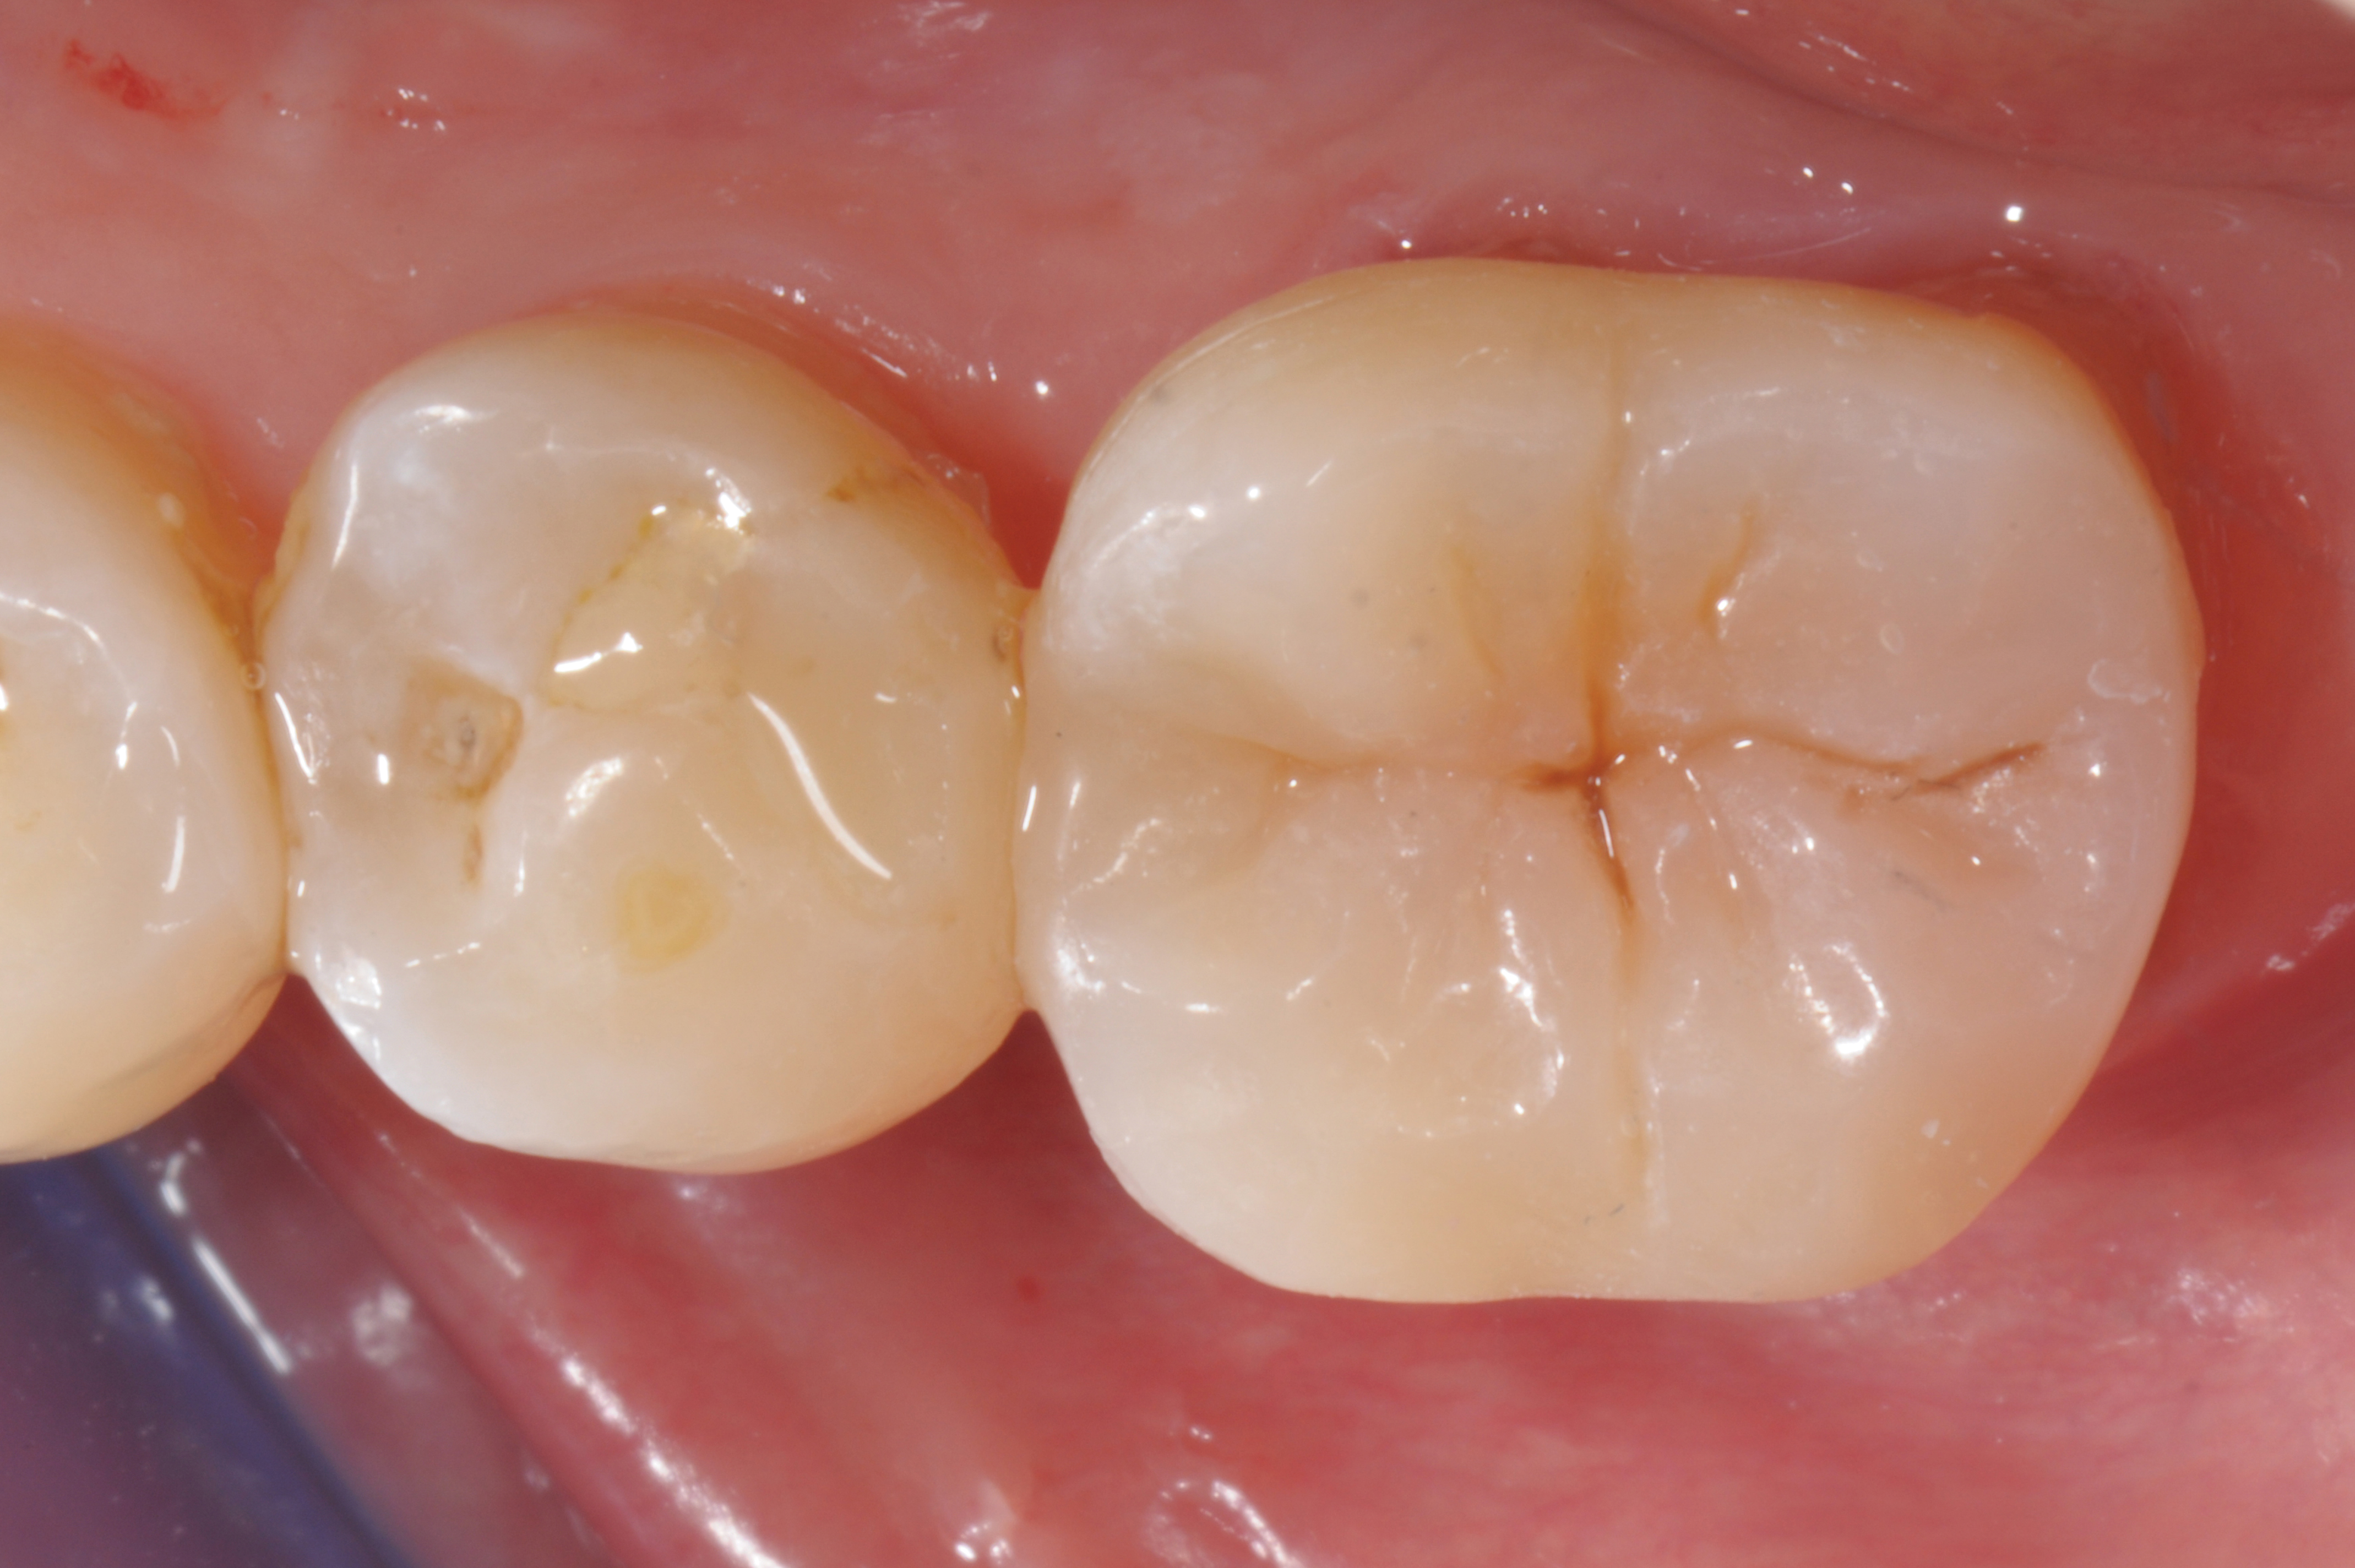

When following a protocol of cementation using an adhesive system, constant rubber dam isolation and careful hand finishing are necessary to provide predictable clinical results (Figure 1 through Figure 4).2

Fig 4. Postoperative view.

Figure 4